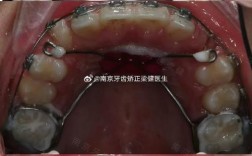

隐形牙套并非“矫正工具之外的新选择”,而是正畸技术中“隐形矫治”的具体载体,与传统钢牙套通过托槽和弓丝施加持续力不同,隐形牙套采用医用高分子材料(如PETG或TPU)制成透明牙套,通过3D打印技术为患者定制一系列“量牙定制”的牙套,每副牙套的形态与前一副存在细微差异,佩戴后可对牙齿施加温和、精准的力,引导牙齿在牙槽骨中缓慢移动,逐步达到排列整齐、咬合正常的目标。

其核心原理在于“分步移动”与“生物力学控制”:通过计算机模拟牙齿移动路径(方案设计阶段需正畸医生评估牙齿情况、咬合关系、面部美学等),将整个矫正过程拆解为多个阶段(通常每副牙套佩戴1-2周,更换下一副进入下一阶段),每阶段移动量控制在0.25mm左右,确保牙齿在生理范围内安全移动,同时减少不适感。